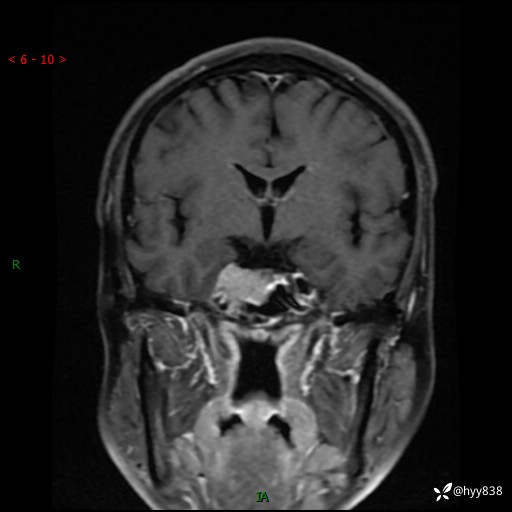

规培和研究生教学片:鞍旁占位,脑膜瘤 VS 侵袭性垂体瘤---结果公布~

现病史:患者半年前无明显诱因出现头痛头痛,呈间断性发作,无复视,无斜视,无头痛头晕,无呕心呕吐,无肢体乏力,无发作性肢体抽搐,无意识改变,无尿量增多,无体毛脱落,无色素沉着,无体重下降,无面容改变,无肢端粗大等,2024-03-26日至当地中医院住院治疗后予以对症处理(具体不详),未见明显缓解,行头颅MRI平扫检查示:“右侧蝶鞍占位,双侧上颌窦炎,双侧下鼻甲肥大,鼻中隔偏曲”,今患者为求进一步诊治来我院,门诊遂以“右侧蝶鞍占位”收住我科。 起病以来,患者精神饮食睡眠可,大小便正常。

MRI增强(外院平扫)